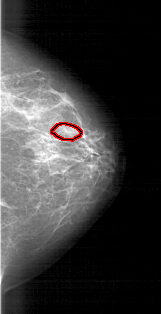

A_1770_1.RIGHT_CC

RIGHT_CC LINES 5011 PIXELS_PER_LINE 2566 BITS_PER_PIXEL 12 RESOLUTION 43.5 OVERLAY

FILE: A_1770_1.RIGHT_CC.OVERLAY

TOTAL_ABNORMALITIES 1

ABNORMALITY 1

LESION_TYPE MASS SHAPE OVAL MARGINS OBSCURED

ASSESSMENT 3

SUBTLETY 3

PATHOLOGY BENIGN

TOTAL_OUTLINES 1

BOUNDARY